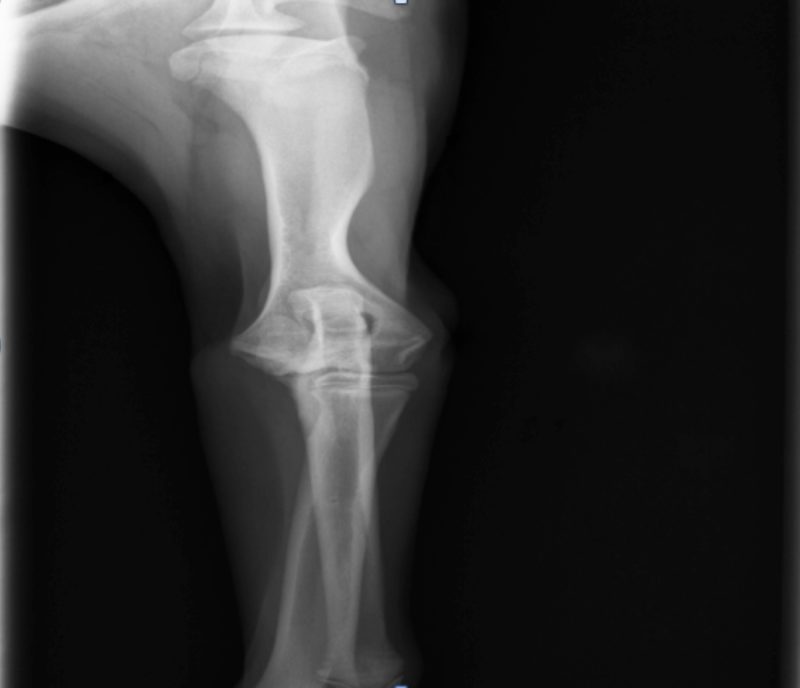

Aaron war munter und aufmerksam, sein Herz-Kreislauf-System und die Palpation des Abdomens waren unauffällig. Seine innere Körpertemperatur lag mit 38,9°C im physiologischen Bereich. Er ging hochgradig lahm auf der linken Vordergliedmaße. Bei der Palpation des linken Vorderbeines konnte man eine deutliche Gelenkfüllung und eine Schmerzhaftigkeit des Ellbogengelenks feststellen. Alle anderen Gelenke waren frei beweglich und nicht schmerzhaft. Es wurde eine Röntgenuntersuchung beider Ellenbögen und Schultern durchgeführt. Die Schultern stellten sich röntgenologisch völlig unauffällig dar. An beiden Ellenbögen konnten Veränderungen in Form einer  Osteochondrosis dissecans (OCD = Knorpelveränderung) nachgewiesen werden, und der linke Ellbogen war hochgradig verdächtig für eine Ellbogendysplasie (ED) mit einem Frakturierten Processus Coronoideus medialis (FCP= abgebrochenes Knochenteil). Aufgrund der röntgenologischen Befunde wurden beide Ellenbögen arthroskopiert. Der Verdacht einer Ellbogendysplasie konnte in der Arthroskopie bestätigt werden. Das abgebrochene Knochenteil wurde entfernt und die Knorpelschuppen der OCD beidseits abgetragen.

Osteophytäre Zubildungen (Arthrosen) wurden am Gelenk diagnostiziert

In den nächsten Tagen erhielt der Hund ein Schmerzmittel und Hyaluronsäure zum Knorpelaufbau und ging regelmäßig zur Physiotherapie. Aaron lief vier Wochen lahmfrei ohne Schmerzmittel. Danach ging er wieder zunehmend lahm. Er zeigte wieder deutliche Gelenkergüsse in beiden Ellenbögen. Es wurde eine Computertomographie-Untersuchung (CT) beider Ellenbögen durchgeführt. Im CT wurden mehrere osteophytäre Zubildungen (Arthrosen) am Gelenk diagnostiziert, welche infolge des permanenten Entzündungsreizes entstanden sind. Weitere knöcherne Veränderungen und eine erneute abgelöste Knorpelschuppe (OCD) konnte nicht gefunden werden.